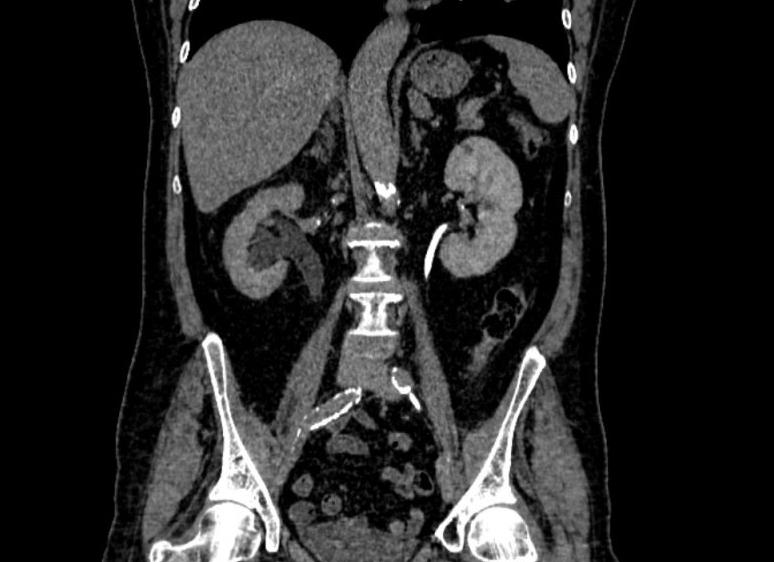

Компьютерные томограммы почек

Суть компьютерной томографии почек и ее разновидности

В основе компьютерной томографии лежит использование рентгеновских лучей и обработка полученных данных сканирования с помощью современных компьютерных технологий. По сравнению с обычным рентгеном, КТ почек считается более информативным диагностическим методом, поскольку с его помощью врач получает четкое и достоверное изображение. Что же происходит во время компьютерной томографии? Рентгеновские лучи проходят вдоль всего тела, а компьютер фиксирует изменения в их энергии. После этого данные обрабатываются и на экран выводится двухмерное изображение просканированных органов. Также КТ иногда делают с контрастным веществом. Оно применяется для получения более отчетливого изображения почек.

КТ почек показывает такой дефект, как измененную их форму, а это, в свою очередь, признак более серьезных заболеваний. На снимке также будут видны почечные кисты и любые другие образования, например, раковые опухоли. Если же исследуемый уже знает, что у него есть новообразования в почках, то с помощью томографии можно определить их размер и характер, узнать, нет ли кровоизлияний или некроза тканей. С помощью мультиспиральной КТ делают исследования очагов возникновения опухолей в кровотоках почек и надпочечников. КТ покажет начинающуюся обструкцию мочевыводящих путей, поликистоз или нарушение оттока мочи. У новорожденных с помощью томографии можно обнаружить проблемы в выделительной системе.

Врач может сообщить, что почки находятся в нормальном состоянии. Это означает, что паренхима почек плотнее чем печеночная, и менее плотная, чем костная. Кроме того, важно исследовать форму почек, их размер и расположение. Местонахождение почек оценивается относительно других органов брюшной полости, то есть учитываются индивидуальные особенности тела.

Нормальные показатели почек на КТ-снимках оцениваются по форме, структуре и локализации внутренних органов. Сравниваются параметры смежных органов для получения точной диагностической картины.

Отклонения от нормы на снимках могут быть самыми разнообразными. Наросты на почке или внутри нее будут иметь отличающуюся плотность тканей, что будет видно по совершенно другой цветовой гамме, благодаря контрастному веществу. Структура почечных сосудов с повреждениями четко просматривается и не оставляет сомнений в постановке диагноза для врачей.

Результатом обследования является послойное изображение почек, надпочечников, прочих органов и структур, составляющих мочевыводящую систему, забрюшинное пространство.

Во время исследования через тело пациента пропускают рентгеновское излучение одновременно в различных плоскостях. Принимающее устройство томографа улавливает отраженные от тканей лучи. Информация обрабатывается при помощи компьютерной программы. На выходе врач получает трехмерное изображение исследуемого органа или системы.